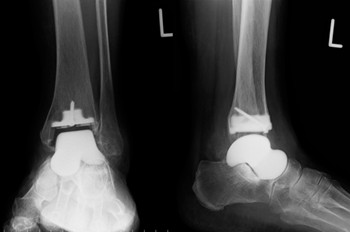

変形性足関節症に対し、薬物療法やインソールで改善しない場合は手術を検討します。当院では、足関節を固定する足関節固定術や、関節の動きを温存できる人口足関節置換術に対応しています。 人工関節に置き換えることで、長年続いていた関節の痛みが大幅に軽減され、歩行能力や日常生活の質(QOL)の改善が期待できます。